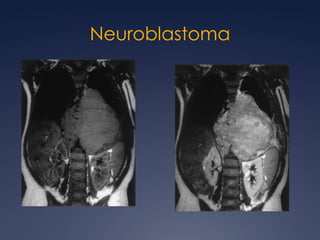

Patología mediastinal no vascularByanka Lorena Pozzo SalvatierraGrupo CT - Scanner